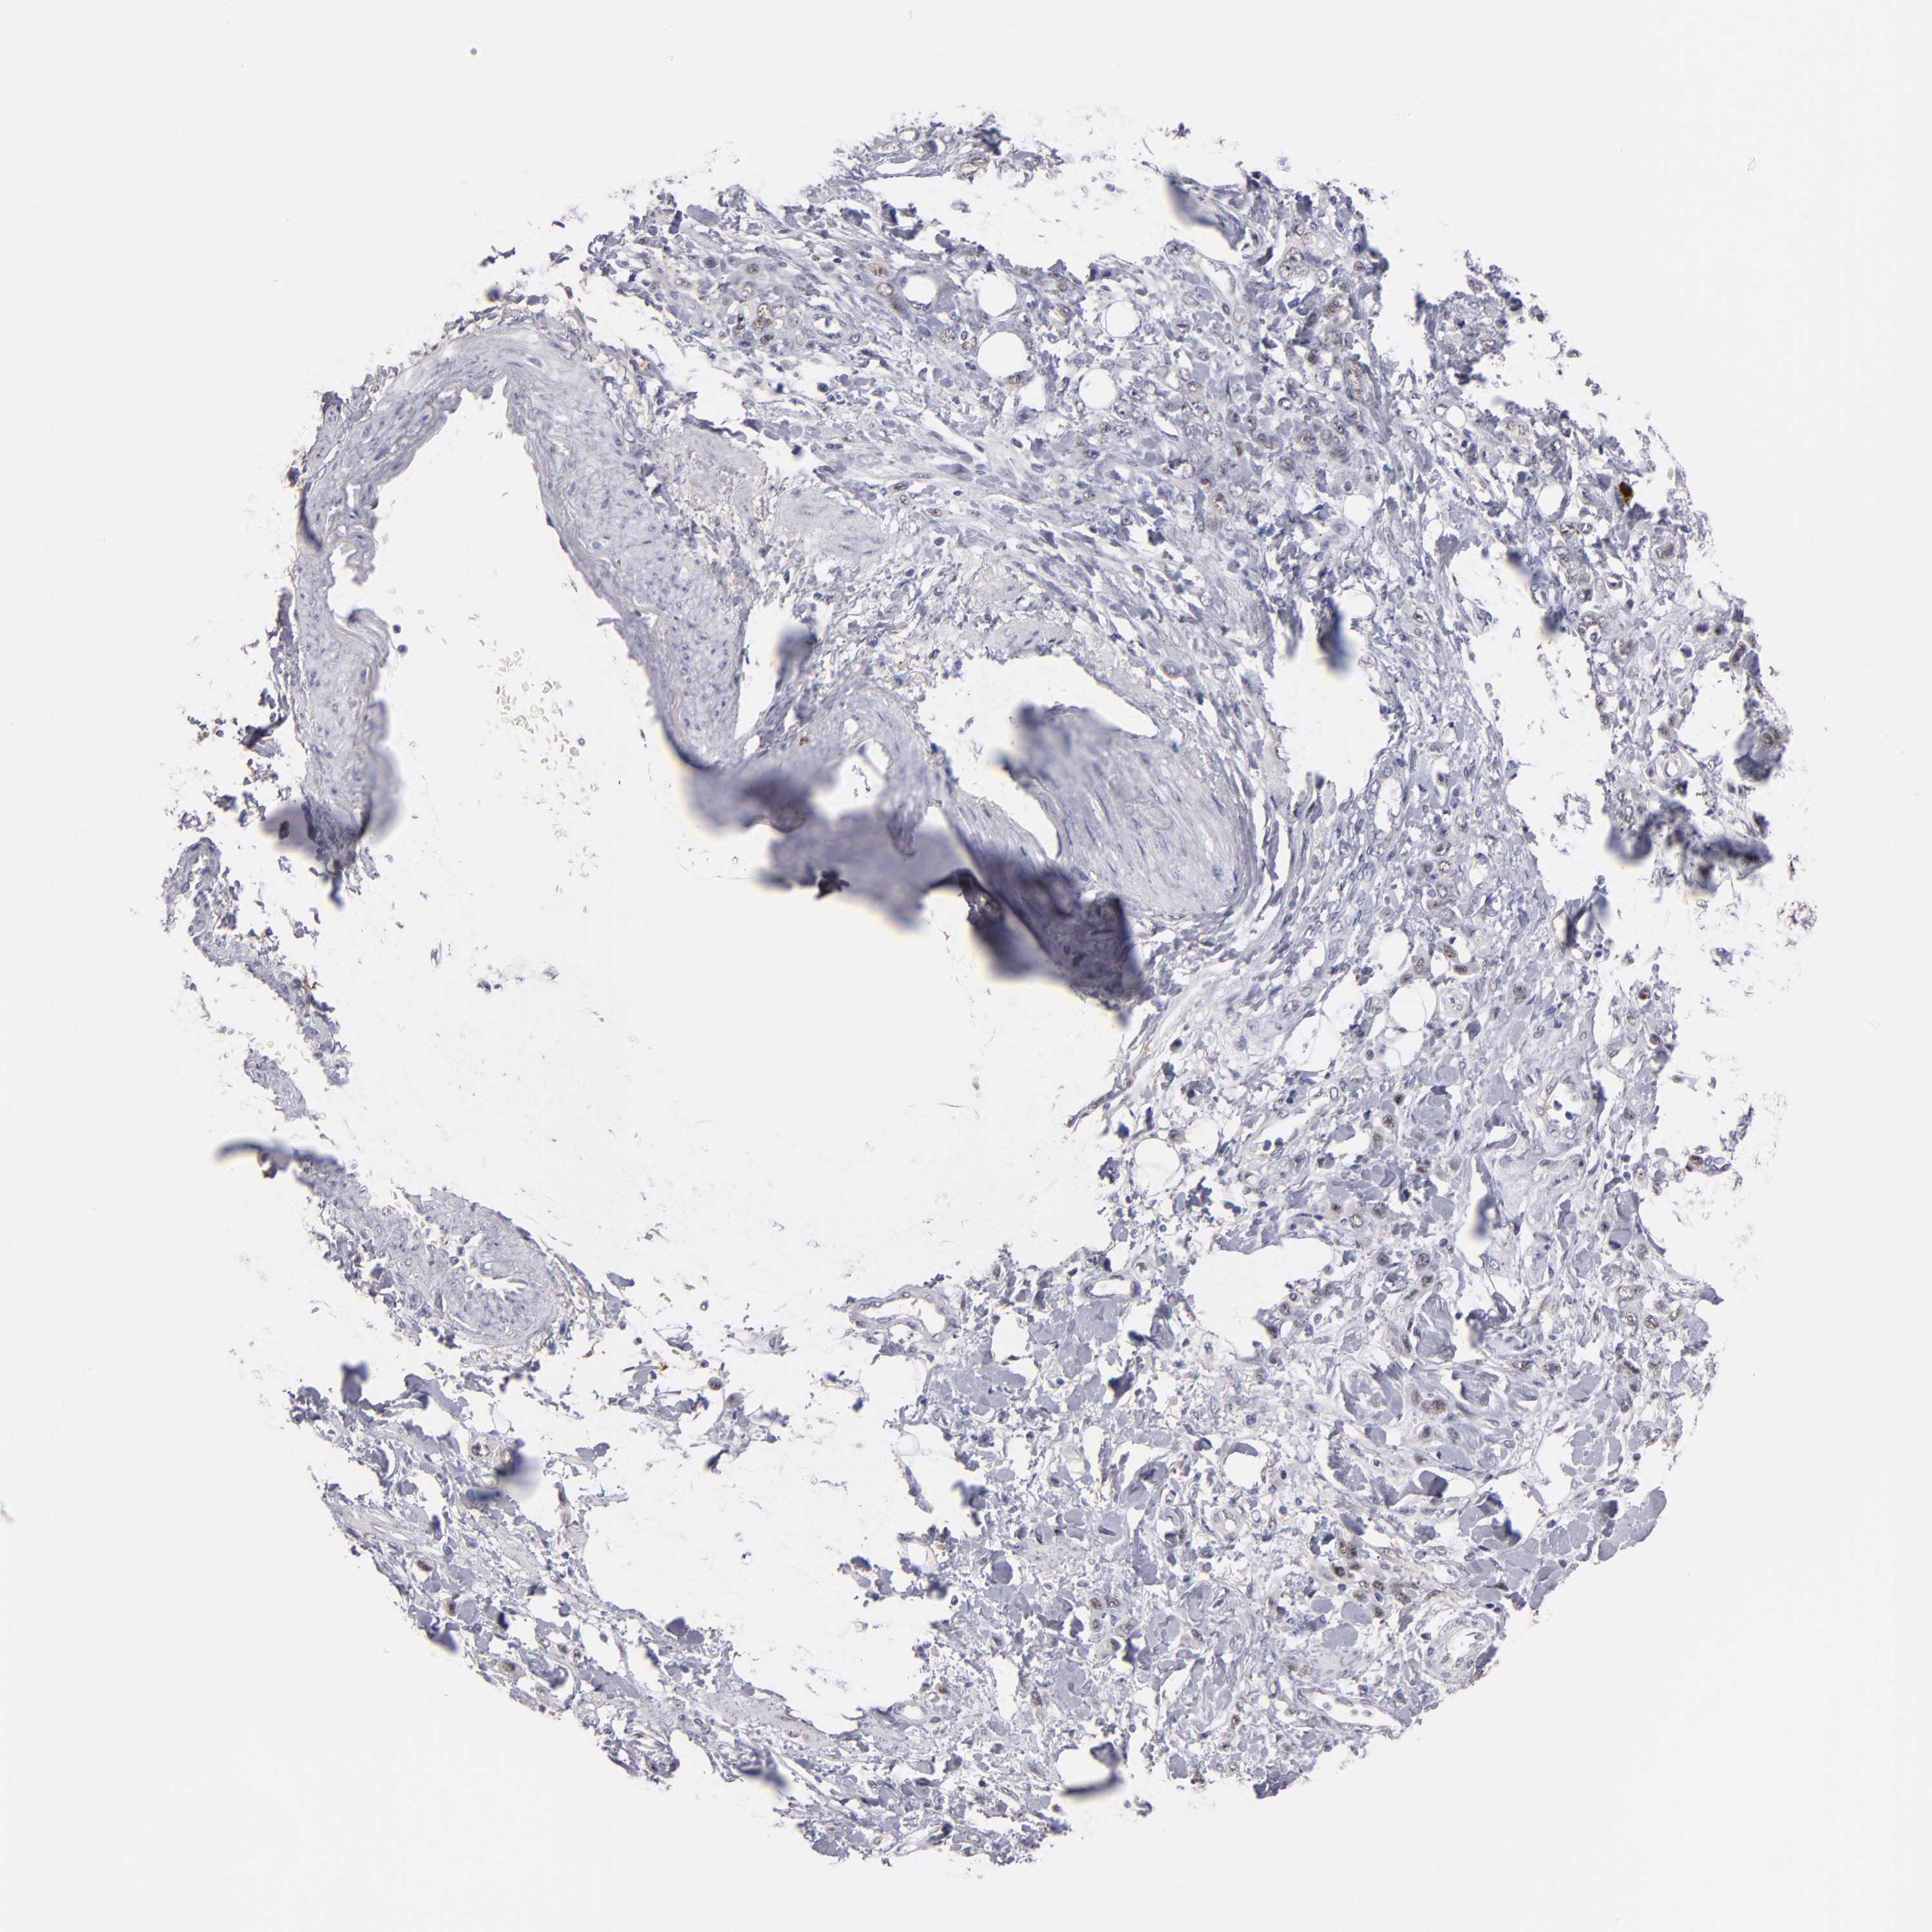

STOMACH CANCER - Protein expressioni

A mouse-over function shows sample information and annotation data. Click on an image to view it in a full screen mode. Samples can be filtered based on level of antibody staining by selecting one or several of the following categories: high, medium, low and not detected. The assay and annotation is described here.

Note that samples used for immunohistochemistry by the Human Protein Atlas do not correspond to samples in the TCGA dataset.

Antibody stainingi

Antibody staining in the annotated cell types in the current human tissue is reported as not detected, low, medium, or high, based on conventional immunohistochemistry profiling in selected tissues. This score is based on the combination of the staining intensity and fraction of stained cells.

Each image is clickable and will lead to virtual microscopy that enables deeper exploration of all samples and also displays staining intensity scores, fraction scores and subcellular localization as well as patient and tissue information for each sample.

Antibody HPA002640

Antibody CAB019291

Antibody CAB080384

Staining

High

Medium

Low

Not detected

Intensity

Strong

Moderate

Weak

Negative

Quantity

>75%

75%-25%

<25%

None

Location

Nuclear

Cytoplasmic/membranous

Cytoplasmic/membranous,nuclear

Adenocarcinoma, NOS

Adenocarcinoma, High grade